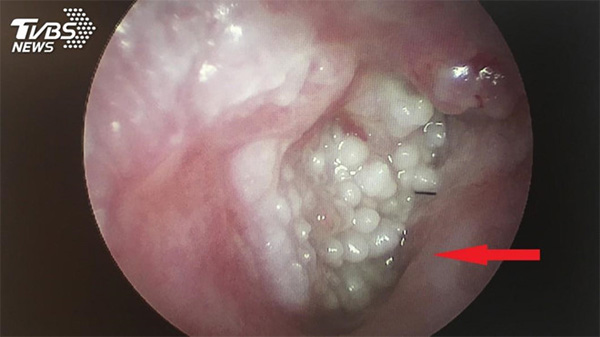

Những nốt sùi mào gà trong tai cụ ông họ Hoàng. Ảnh: TVBS.

Bác sĩ Ngô Thiệu Khoan, khoa Tai Mũi Họng, Bệnh viện Nam Đầu, cho hay sau khi dùng ống soi tai, các bác sĩ phát hiện trong lỗ tai của người đàn ông này có nhiều mụn thịt mọc chi chít. Chúng đã lấp toàn bộ lỗ tai nên ảnh hưởng đến thính lực.

Những mụn thịt này được chẩn đoán là sùi mào gà - một bệnh xã hội thường gặp ở vùng sinh dục. Điều này khiến bác sĩ Ngô rất bất ngờ và tò mò vì đây là lần đầu tiên ông gặp một bệnh nhân bị sùi mào gà trong lỗ tai.